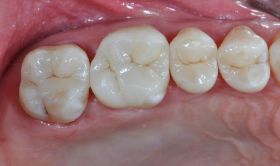

Résultat 1mois après la pose